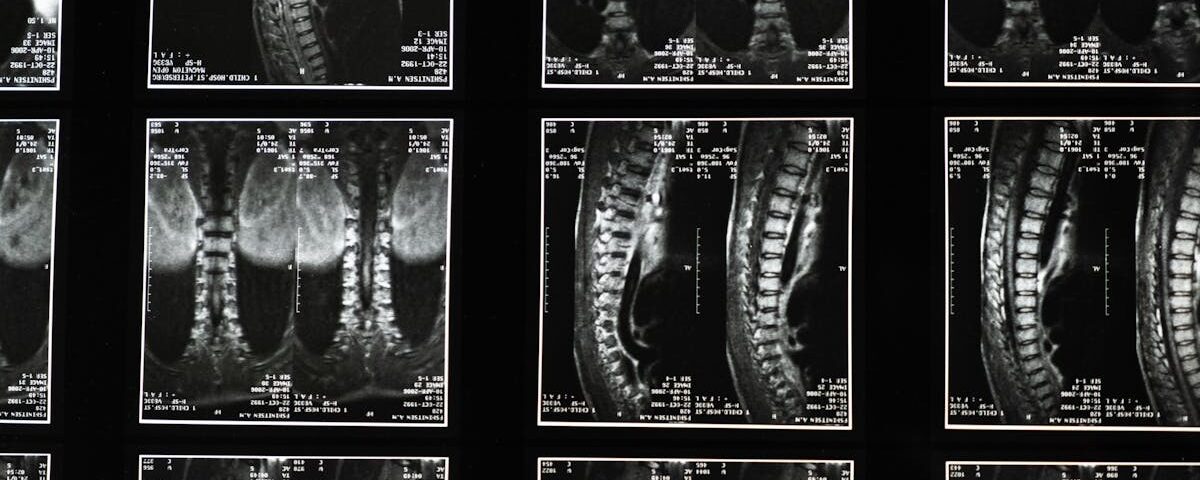

Un diagnostic précis est essentiel pour établir le traitement adéquat. Cela nécessite souvent des examens médicaux spécifiques, tels que des IRM ou des échographies, pour identifier avec précision la source de la douleur. Ignorer ce diagnostic peut prolonger la souffrance et retarder le processus de guérison.

La première étape dans la gestion de la sciatique consiste à obtenir un diagnostic médical complet. Un professionnel de la santé, comme un spécialiste en médecine manuelle ou un ostéopathe, pourra identifier l’origine des douleurs sciatiques et la nature des lésions dont le patient souffre. Pour ce faire, des examens médicaux appropriés peuvent être nécessaires. Ces investigations comprennent des examens d’imagerie, comme des IRM ou des scanners, qui permettent de visualiser l’état des disques intervertébraux et des structures environnantes.